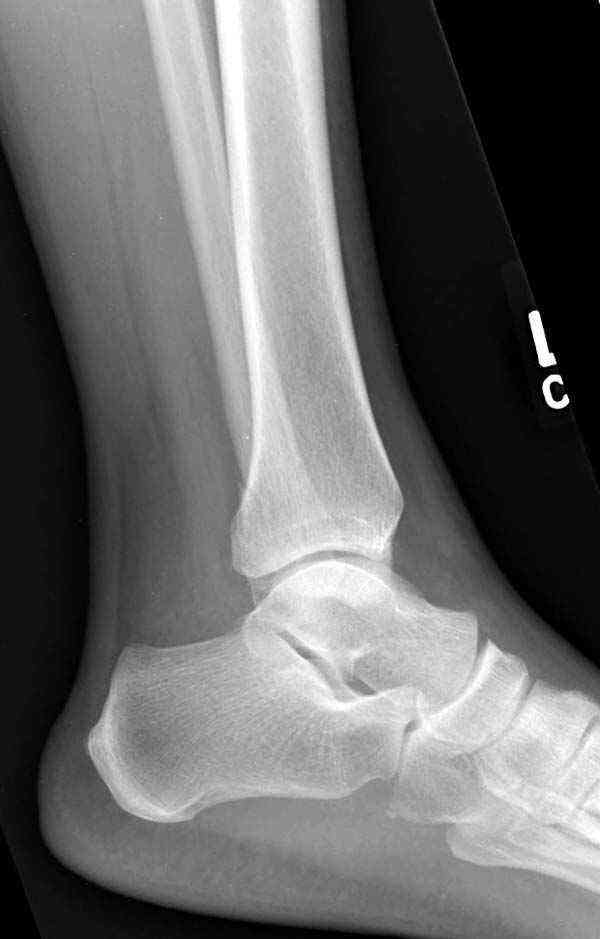

Нет первичных снимков, перелом очень низкий и под большим сомнением диагноз разрыва синдесмоза. Медиальная сторона отрепонирована на "хорошо" и, по-видимому, прорезание проволоки произошло во время операции. Без снимков трудно судить о высоте малоберцовой, а лодыжка находится в варусе. Лагирование получилось, но возле тонких шурупов передне-задний шуруп выглядит немного тяжеловато.

Здесь несколько частных случаев: перелом голеностопа со сравнительными снимками и разрыв синдесмоза, а также медиальная Hook пластина.